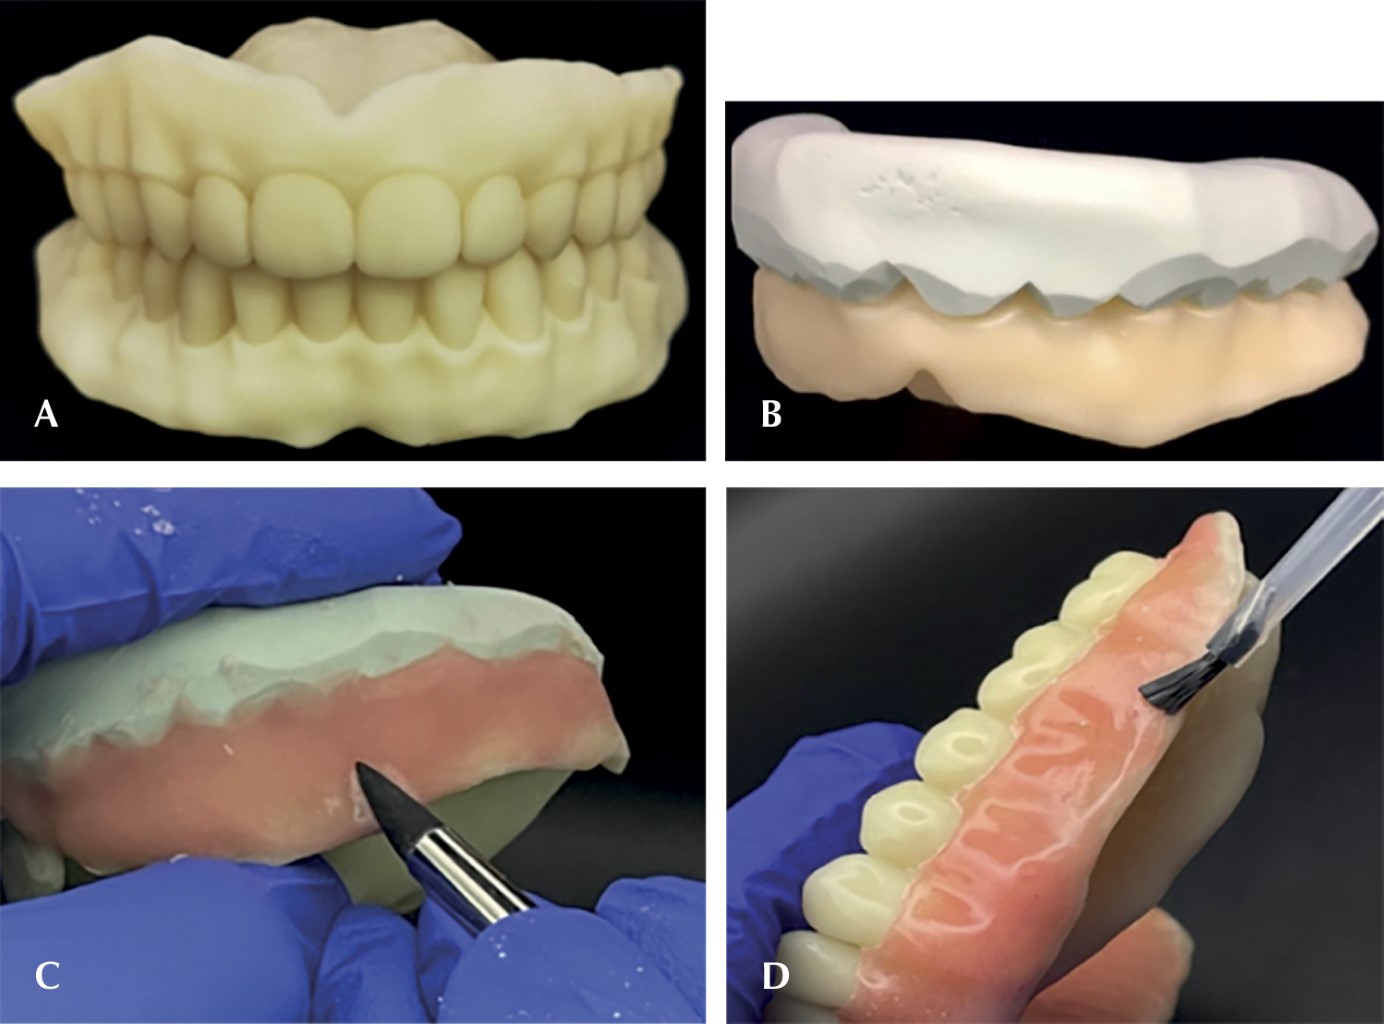

Se imprimieron ambas prótesis inmediatas en resina fotopolimerizada a base de metacrilato color A2 (Temporary CB Resin de la marca Formlabs®) (Figura 3). Se llevó a cabo con la impresora 3D modelo IBEE de la marca UNIZ® utilizando un grosor de capa de 25 micras.

Se caracterizó la prótesis inmediata con acrílico termocurado color R5V. Para evitar superposiciones de acrílico en la dentadura, se colocó vaselina en las piezas dentales y se cubrió con una llave de silicona (se utilizó la marca Speedex®). Al terminar, se recubrió la prótesis en toda su superficie con sellante de composite de alta penetración de la marca PermaSeal® (Figura 3).

Se realizó la entrega de las prótesis inmediatas (Figura 4). Al colocar se utilizó un acondicionador de tejidos para bases y rebases de la marca Softy®. Se colocó el material en la prótesis inmediata superior y posteriormente en la inferior y con ello se le indicó a la paciente que mordiera. Después se realizaron ajustes en la línea de la base de la dentadura y ajustes oclusales (Figura 4).